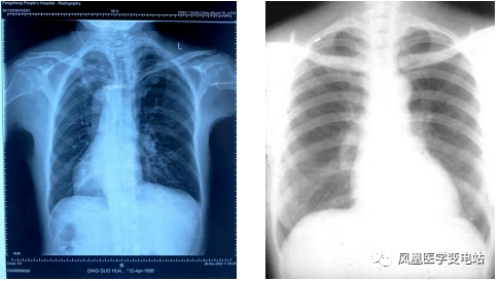

【影像检查】

特别的右位心摄片 正常左位心摄片

结合这些检查资料,丁先生被诊断为:阵发性心房颤动,镜面右位心。